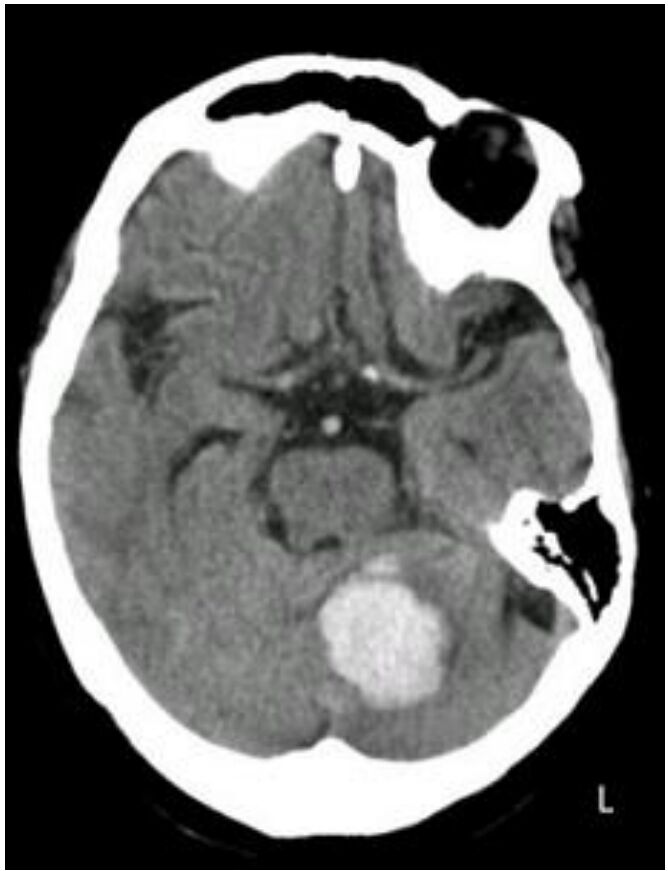

44.一位出血性中風病患入院後的影像檢查如下圖,該病患最不可能出現下列何項臨床檢查結果?

題目右上角的黑色圓形空洞,是眼睛,切片高度的重要landmark如下圖:

對照可知,白色出血區域是左側小腦